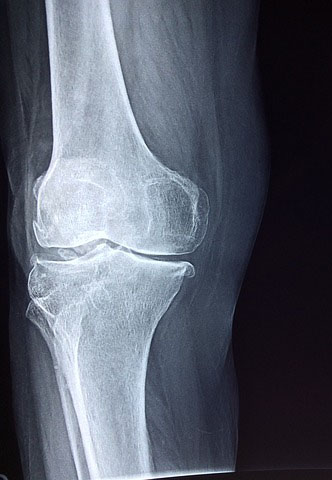

1. 연골 감소 억제

콘드로이친은 관절과 연골을 분해하는 효소를 억제하는 기능이 있으며 새로운 연골 재생을 촉진해 줍니다.

연골을 분해하는 효소를 엘라스타아제라고 하는데 콘드로이친은 이 엘라스타아제를 억제하여 연골이 감소하는 것을 막아줍니다.

2. 관절 통증 감소와 보행 능력 향상

다양한 연구에서 콘드로이친을 섭취했을때 관절 통증이 감소하고 보행 능력이 향상되는 것을 확인했다고 합니다.

하지만 1년 3개월 동안 섭취한 결과이며 콘드로이친은 장기가 꾸준히 섭취해야 효과를 볼 수 있습니다.